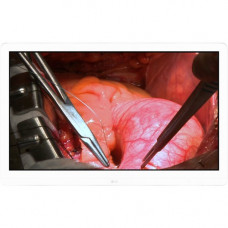

8MP SURGICAL MONITOR A Display Optimized for the Operating Room The superior detailed picture quality of the LG surgical monitor meets operating room requirements. With its 27-inch IPS 8MP display, the LG surgical monitor improves work efficiency not only by enabling detailed observation but also by displaying multiple imaging applications. IPS & 115% of sRGB Enhancing Deep Red The 8MP IPS display not only enables detailed observation of previously hard-to-see regions but also displays multiple imaging applications. In particular, the LG surgical monitor provides brightness and sRGB over 99% to ensure accurate color reproduction in the surgery room. Moreover, by adding a deep red color spectrum, the LG surgical monitor assures color expression of the red spectrum. DICOM Part 14 & Brightness Stabilization With various features to stabilize and adjust the brightness to meet standard viewing requirements, the LG surgical monitor carefully measures and sets every grayscale tone to create a monitor compliant with DICOM Part 14 to ensure visual accuracy and consistency. Furthermore, LG''s surgical monitors offer stabilized brightness settings that quickly adapt during the surgical procedure to correspond to local lighting conditions.DICOM Part 14, published by the National Electrical Manufacturers Association (NEMA) and the American College of Radiology (AC R), provides strict guidelines for performing grayscale display function calibration and quality assurance tests on displays used in medical imaging applications.Flicker Safe Flicker Safe reduces on-screen flickers, which helps minimize eye strain and eye fatigue. By combining Flicker Safe with the proven picture quality of IPS technology, users can comfortably work throughout the day.Dustproof & WaterproofThe LG''s multi-coated glass is highly durable and scratch-resistant and protects the panel during surgical procedures. The front panel is IP35 rated and the back panel is IP32 rated, protecting against dust, water or fluids that may contact it during an operation. In addition to the waterproofing safeguards, its flat surface allows for easy cleaning of the 8MP panel and control buttons.Anti-reflection & Optical Bonding GlassAn LG surgical monitor with optically bonded glass significantly reduces internal reflection between the cover glass and the LCD to enhance accuracy. Improved anti-reflection ability enables displays to look brighter and sharper for the highest image quality. Now you can accurately judge what you see on-screen with high legibility and definition during the operation without eyestrain.